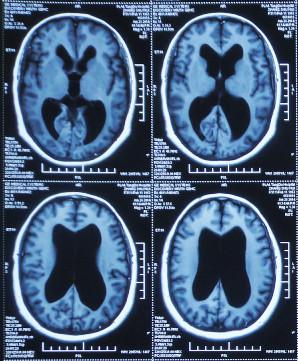

患者2014年6月20日出现持续头晕的症状,不能自行缓解,于2014年6月24日和6月26日分别就诊于甘肃省平凉县某医院和陕西省西安某医院,进行了头颅MRI和头颅CT示脑室扩张,脑积水(图-1、图-2)。

图-2:2014年6月26日头颅CT

为治疗脑积水,于头晕发病8天后即2014年6月28日,就诊于陕西省西安某三甲医院神经外科,当天查头颅MRI:脑积水(图-3)。

图-3:2014年6月28日头颅MRI